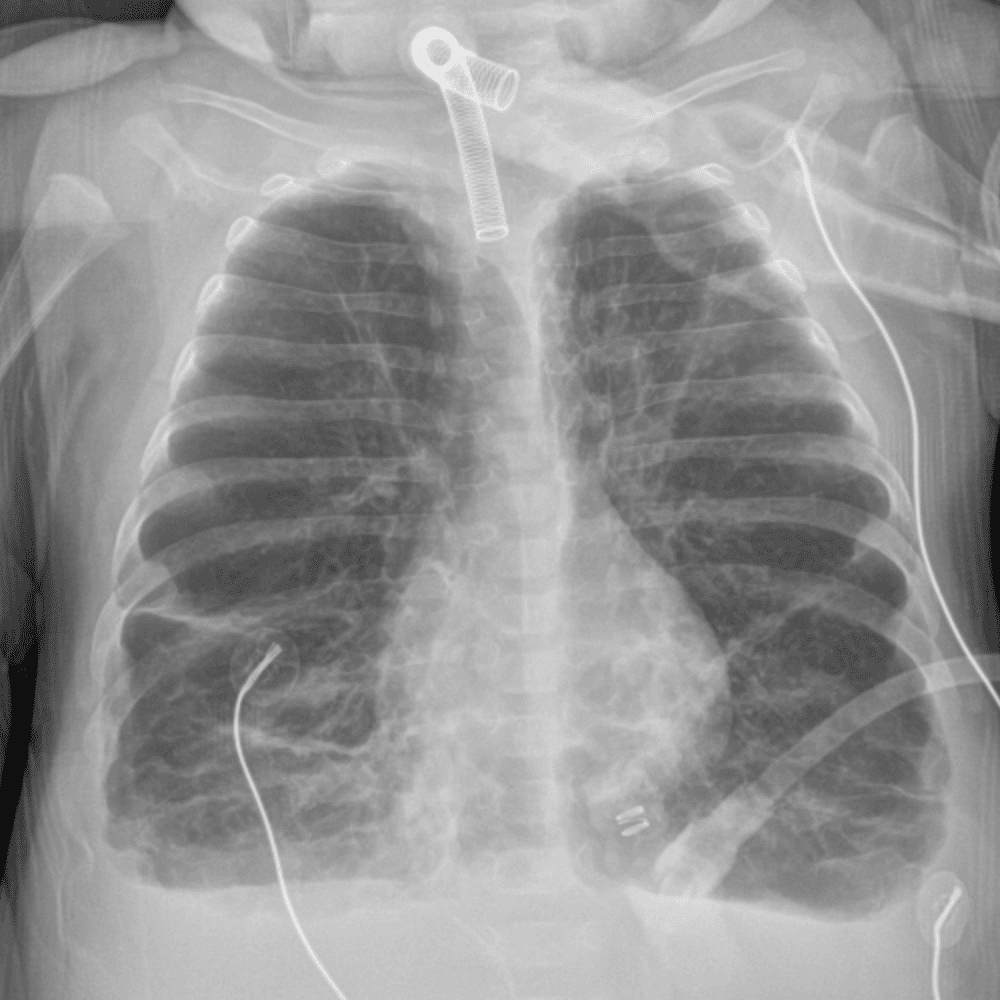

Peds Chest

Practice

Simulates call by including subtle or difficult cases and some normals.

50 cases